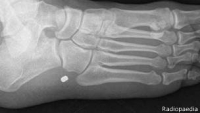

En 2005, Frank Gaillard, un estudiante de medicina comenzó a subir sus apuntes a Internet, un proyecto que ahora, 10 años después, ha resultado en una web en la que comparte imágenes de rayos X que pueden ayudar a millones de profesionales de todo el mundo.